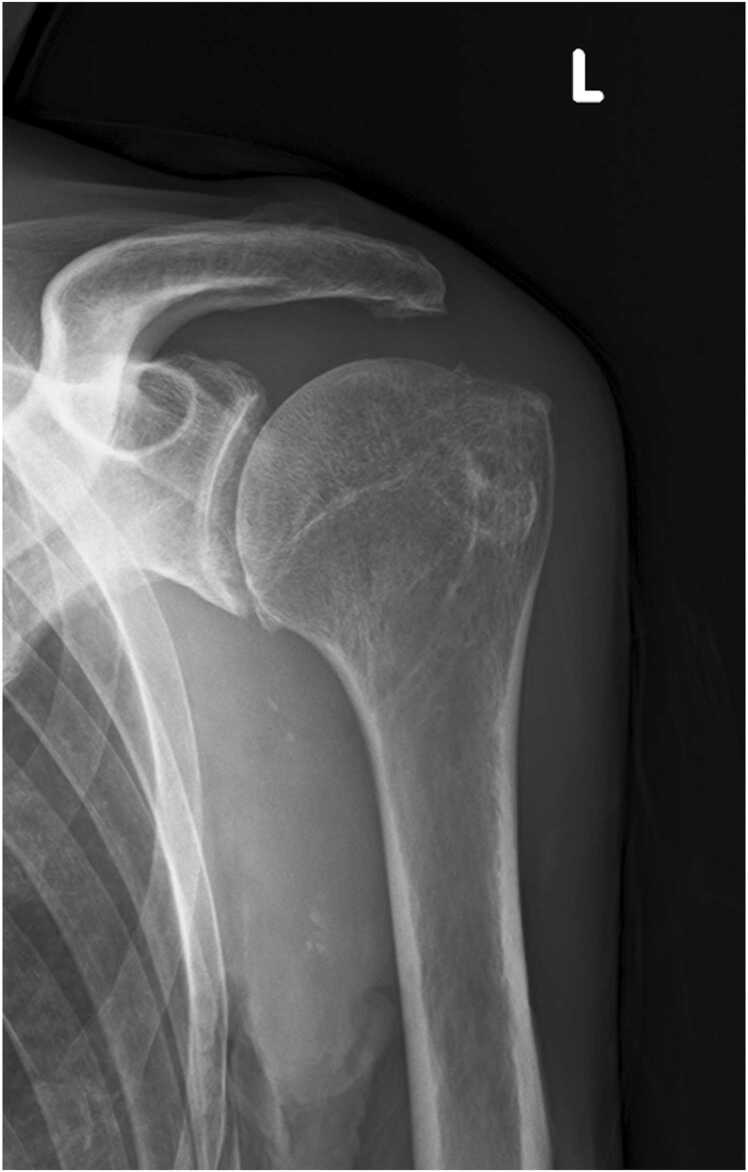

Scrub typhus (tsutsugamushi disease) is an acute febrile illness caused by Orientia tsutsugamushi, often found in Asia and Oceania. The presence of an eschar, characterized by a crust, is a key diagnostic finding. Many symptoms of this disease are already known, however reactive arthritis following scrub typhus is very rare. Here, we present a case of 79-year-old man who was referred to our hospital because of continuous fever and left shoulder pain. We found 4-fold rise in Orientia tsutugamushi-specific IgG titer using paired serum samples and Orientia sp. genes by real-time PCR from a crust of right thigh. And the left shoulder joint image was consistent with aseptic arthritis; thus we diagnosed as scrub typhus with reactive arthritis. This case highlights the importance of recognizing reactive arthritis as a symptom of scrub typhus. In this report, we also review published cases of reactive arthritis associated with scrub typhus, and we suppose that this arthritis related to this infection may recover after antibiotic use and have a good prognosis. Physicians' awareness of newly appeared arthritis may contribute to facilitate early diagnosis, and may improve the course of such patients.